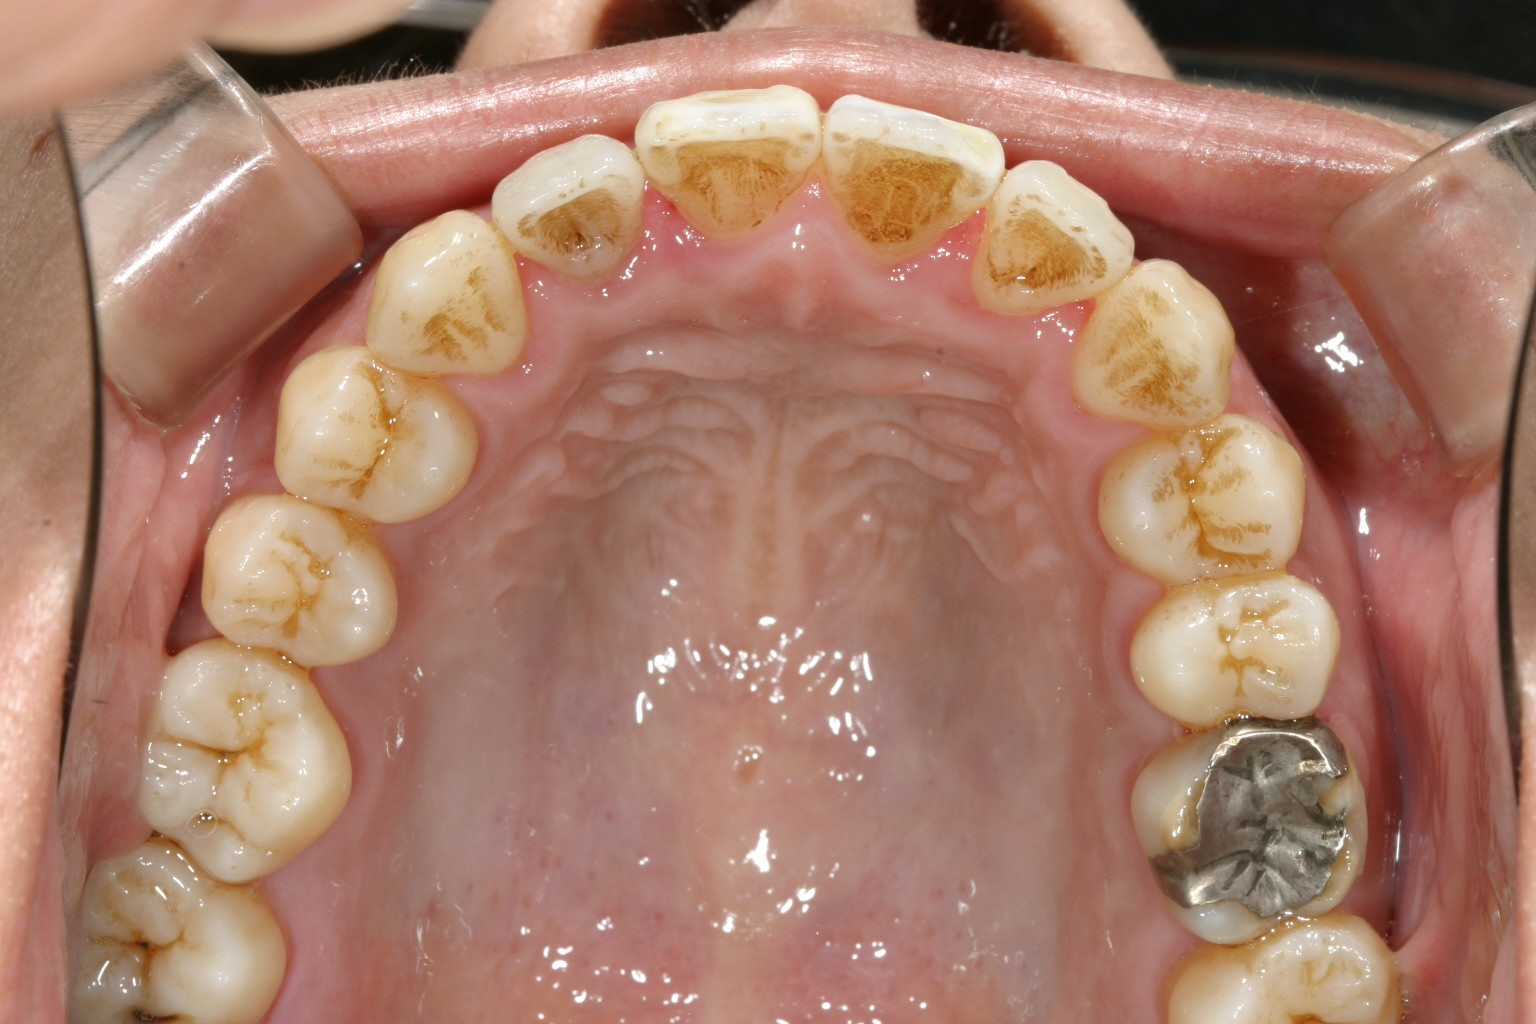

犬歯間が狭い為に上顎前歯が乱れています。

上と下の歯が閉じず開咬状態です。

1年9カ月後です。 前回の写真よりもアーチがU字になってきているのが分かります。